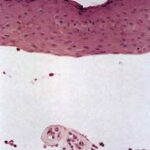

The histologic changes in the skin lesions are the same in all six types of porphyria with cutaneous lesions. Differences are based on the severity rather than on the type of porphyria. Homogeneous, eosinophilic material is regularly observed, and bullae are present in some instances. In addition, sclerosis of the collagen is present in old lesions .

In mild cases, homogeneous, pale, eosinophilic deposits are limited to the immediate vicinity of the blood vessels in the papillary dermis . These deposits are best visualized with a PAS stain, being PAS positive and diastase resistant.

In severely involved areas, which are most common in erythropoietic protoporphyria, the perivascular mantles of homogeneous material are wide enough in the papillary dermis to coalesce with those of adjoining capillaries. In addition, deeper blood vessels may show homogeneous material around them, and similar homogeneous material may be found occasionally around eccrine glands . PAS staining demonstrates this material particularly well. In some instances, it also contains acid mucopolysaccharides, shown with Alcian blue or the colloidal iron stain , or lipids, demonstrable with Sudan IV or Sudan black B . In addition, the PAS-positive dermal­epidermal basement membrane zone may be thickened .

The bullae, which are most common in porphyria cutanea tarda and least common in erythropoietic protoporphyria, arise subepidermally . Some blisters are dermolytic and arise beneath the PAS-positive basement membrane zone ; others form in the lamina lucida and are situated above the PAS-positive basement membrane zone . It has been suggested thatthe blisters in porphyria cutanea tarda in mild cases arise within the junctional zone but that in severe cases they form beneath the PAS-positive basement membrane zone and thus heal with scarring . It is quite characteristic of the bullae of porphyria cutanea tarda that the

dermal papillae often extend irregularly from the floor of the bulla into the bulla cavity (104,122). This phenomenon, referred to as festooning, is explained by the rigidity of the upper dermis induced by the presence of eosinophilic material within and around the capillary walls in the papillae and the papillary dermis.